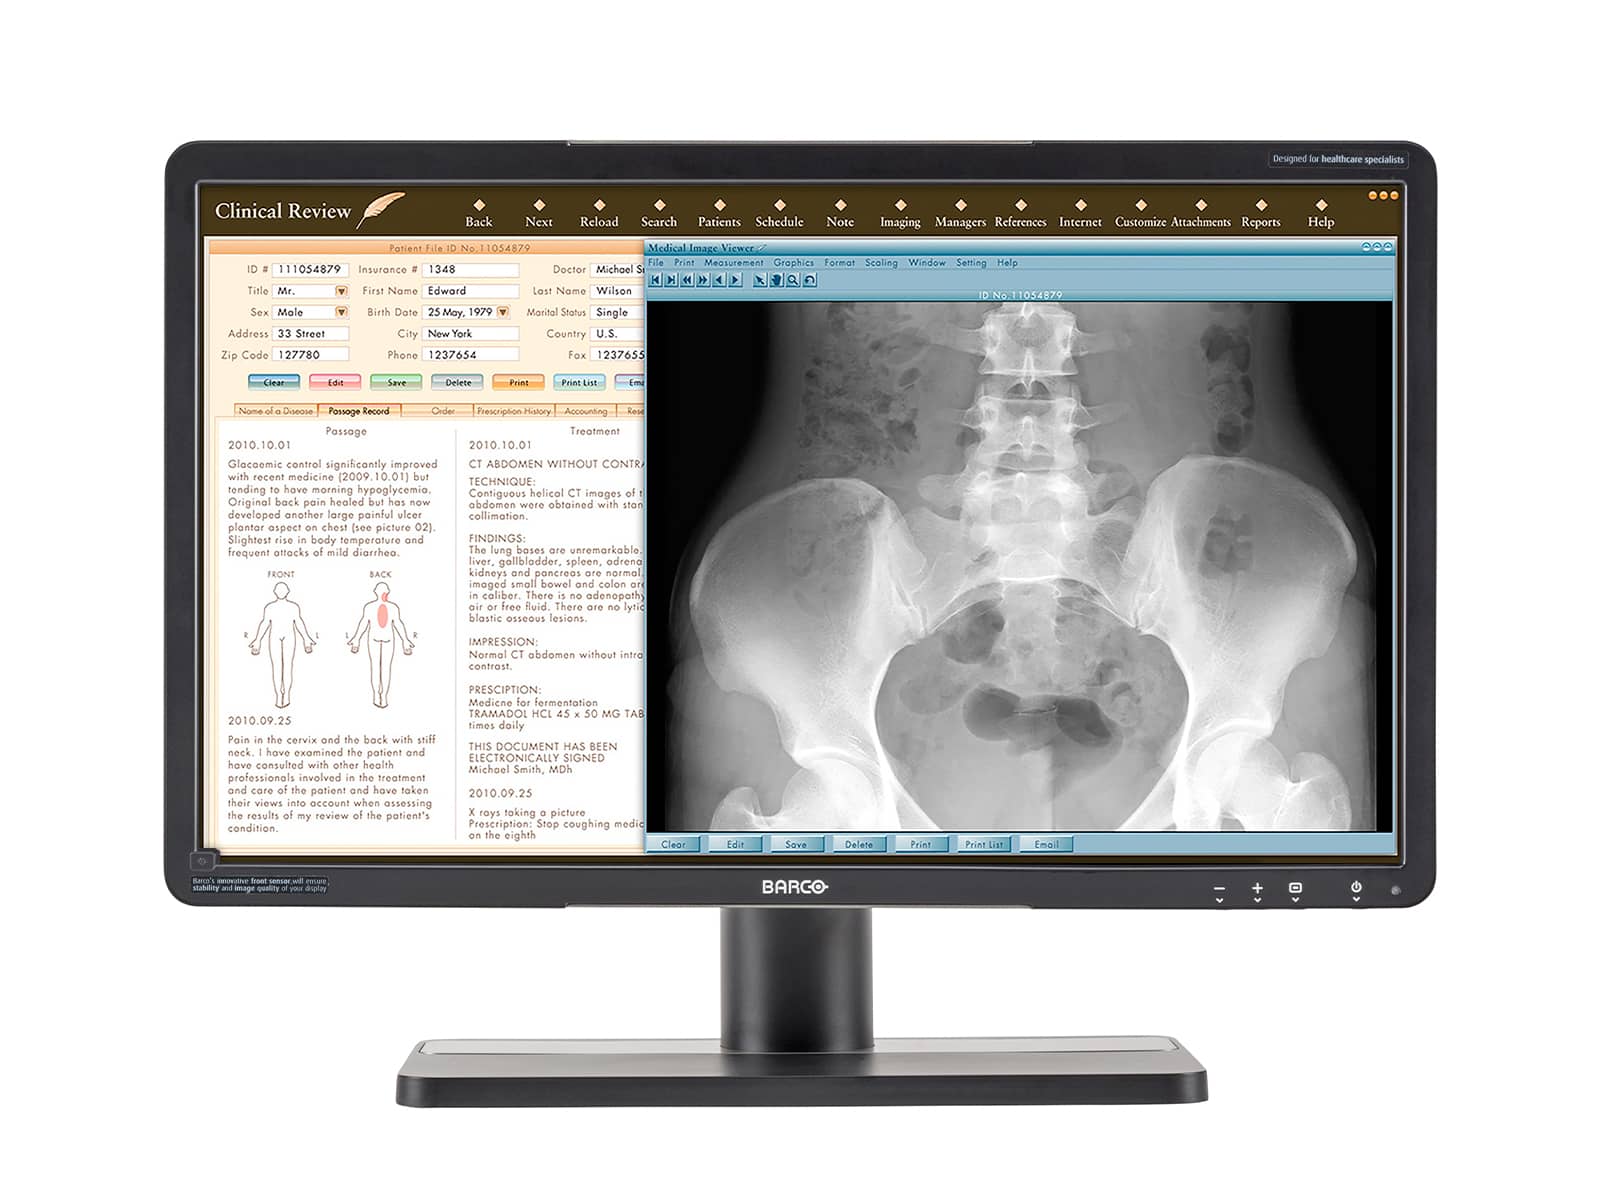

Barco Coronis Fusion MDCC-6430 6MP 30" Color LED General Radiology PACS Display

Barco Nio MDNC-3321 3MP 21" Color LED General Radiology Diagnostic PACS Display

Barco Coronis Fusion MDCC-6530 6MP 30" Color Medical Diagnostic Radiology Monitor

Barco Nio MDNC-3421 3MP 21" Color LED General Radiology PACS Display

Barco Coronis Fusion MDCC-6330 6MP 30" Color LED General Radiology PACS Display